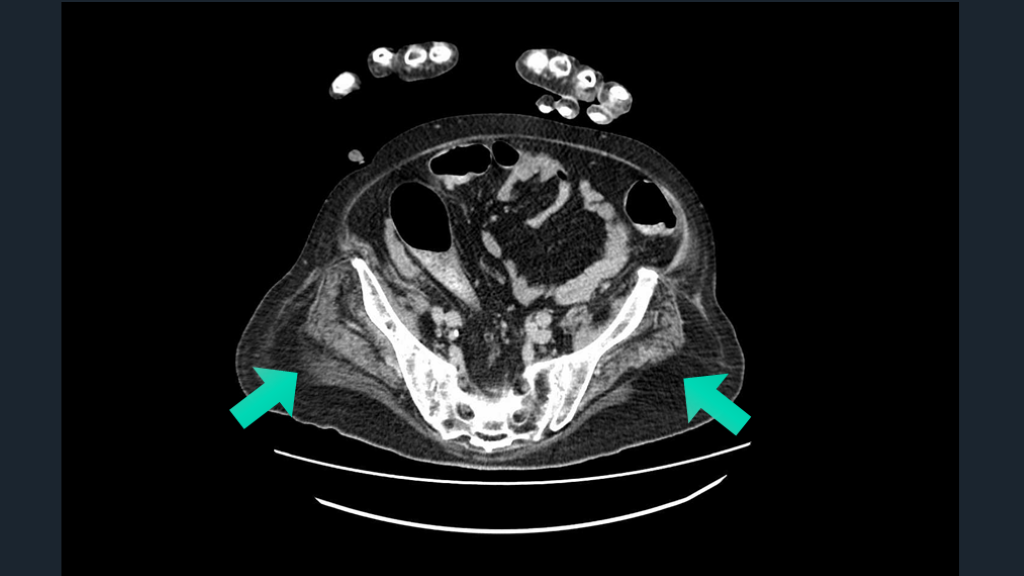

脊髄障害は わかりにくかったりする。 運動感覚障害・膀胱直腸障害を ヒントに。CTでの膀胱所見も。 TIPS

CTで膀胱見てみる。 しっかりした脊髄障害では膀胱直腸障害はないか?を意識して所見を確認する。 CTでの膀胱が緊満しているさまもみる。 脊髄梗塞の鑑別には、CTで大動脈解離も気にする。 解説 Neurologia . 2023;38(6):391-398.

Ochsner J. 2015;15(1):70–73. CTで膀胱拡張を確認